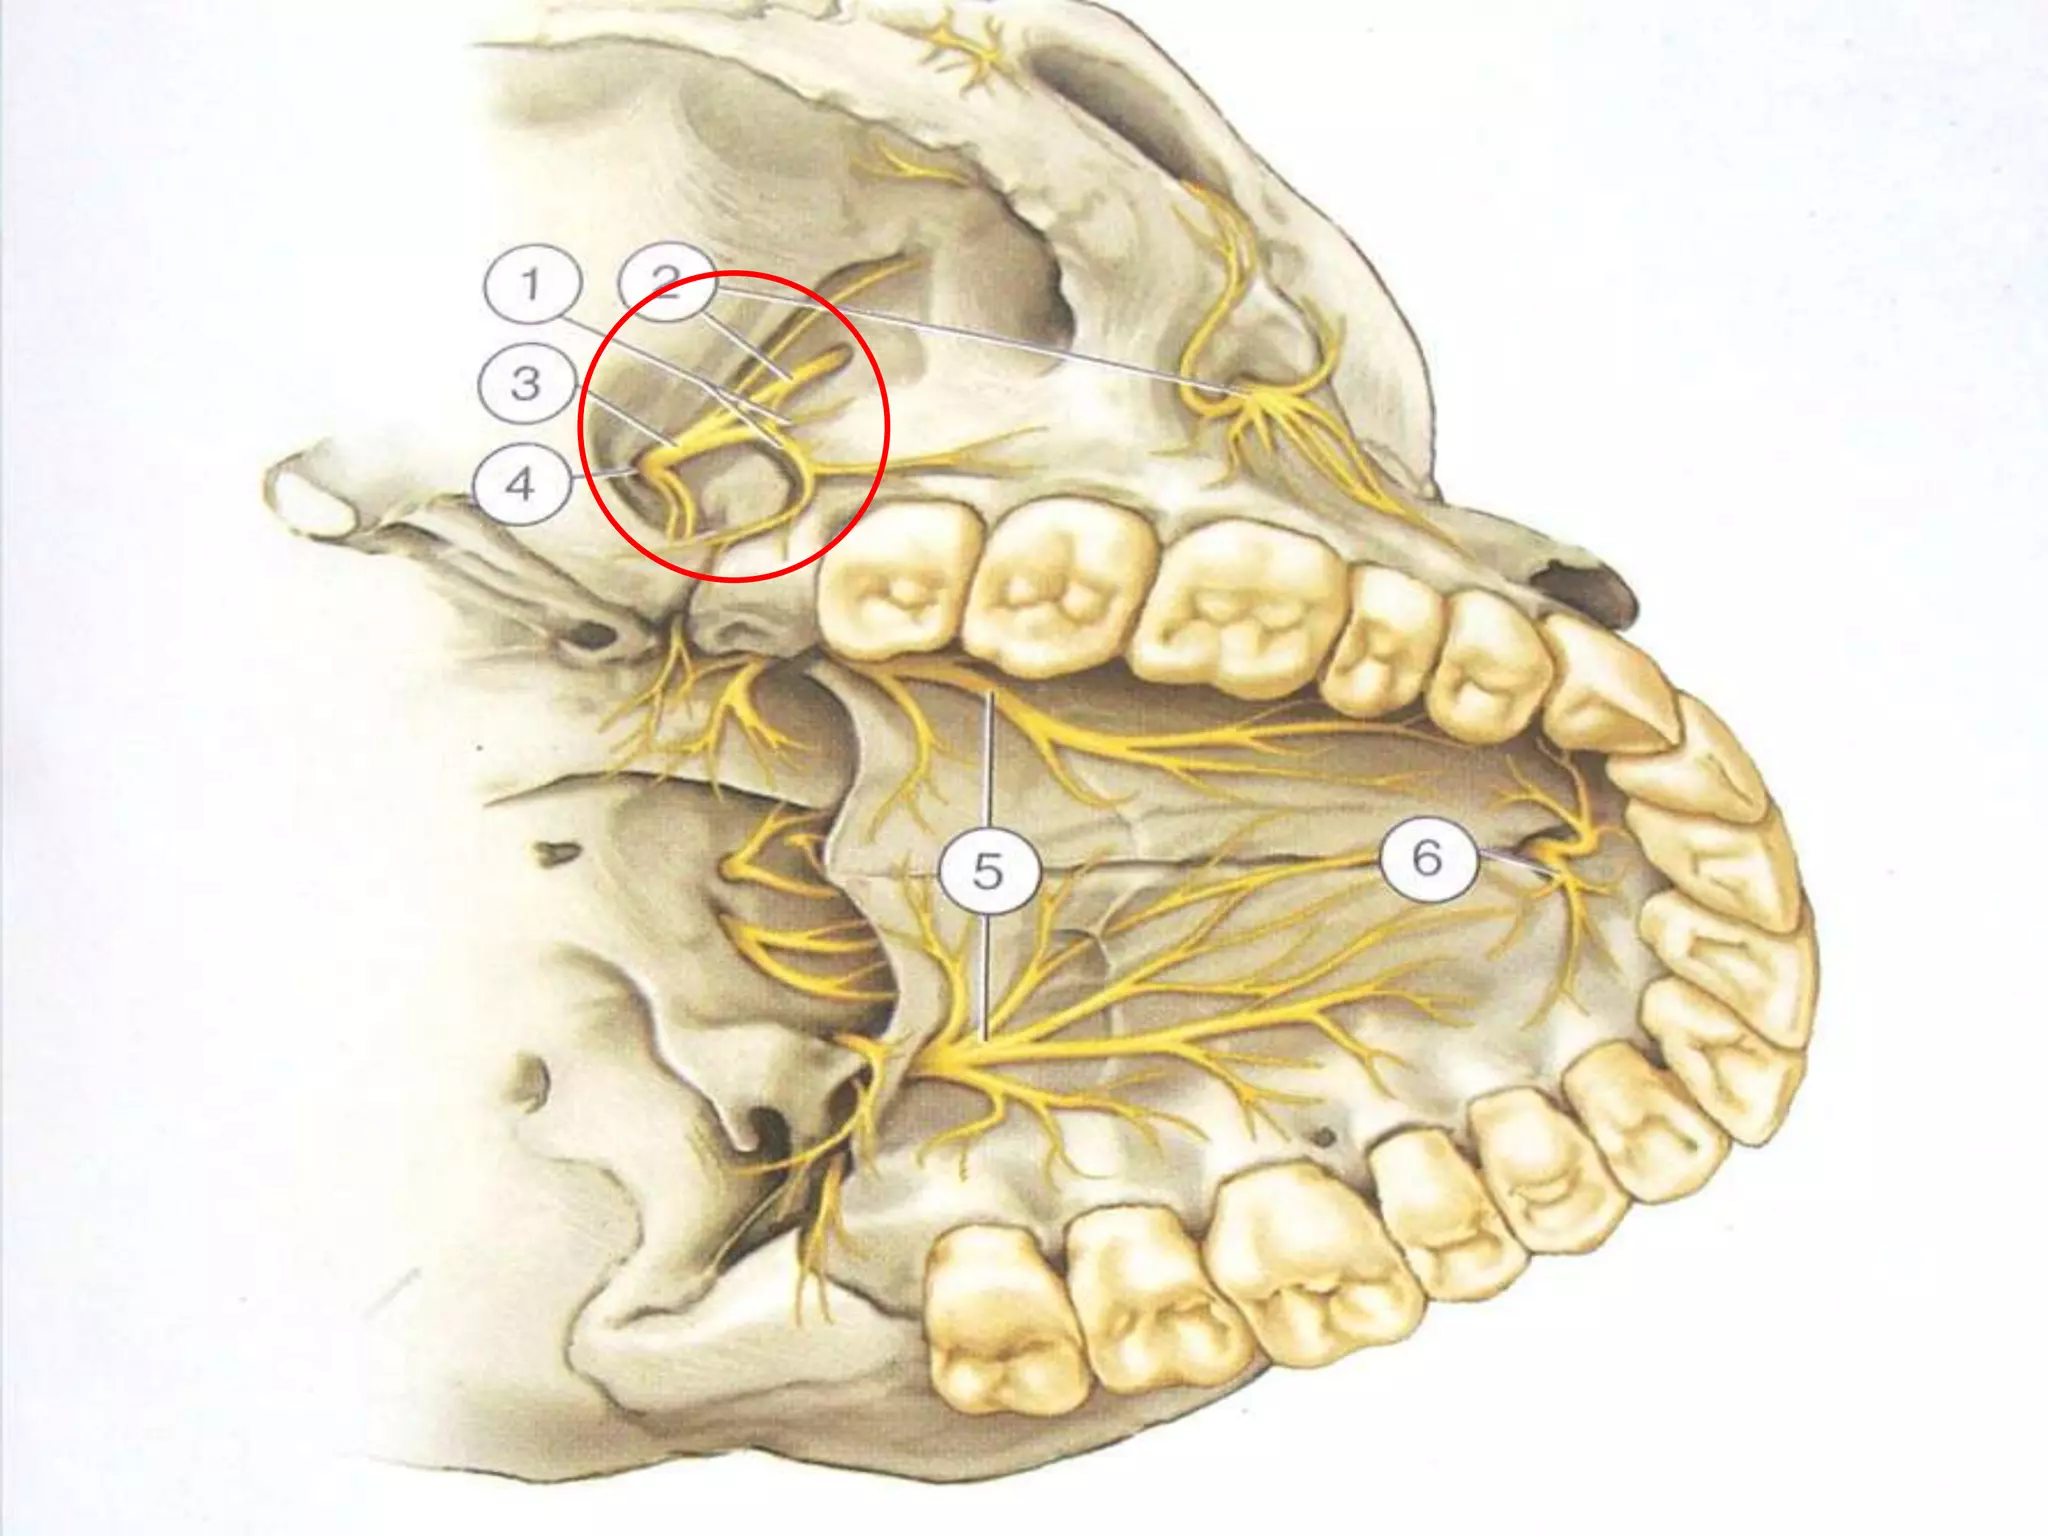

1. Trigeminal ganglion

2.CILIARY GANGLION:

sensory for orbit

3. PTERYGOPALATINE GANGLION:

(Synonym: ganglion pterygopalatinum,

meckel's ganglion, nasal ganglion,

sphenopalatine ganglion)

PTERYGOPALATINE GANGLION: connected to maxillary nerve in

infratemporal fossa

sensory to orbital septum, orbicularis and nasal cavity ,

maxillary sinus , palate , nasopharynx.